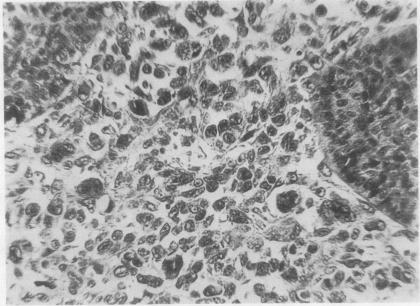

Carcinosarcoma accounted for 0.27% of nearly 3000 lung cancers examined in this department. All the patients were men aged between 44 and 62 years, and a majority of the tumours occurred in the left lung. Three patients died within six months of lung resection and in each case a postmortem examination was performed. In seven the carcinomatous component was a squamous-celled growth, and in one columnar-celled; the histology of the sarcomatous element varied. Carcinosarcomas form a distinct group of malignant lung tumours. In five cases sarcomatous transformation of the stroma had occurred and was considered to be the usual means by which the mixed type of growth arises. The other three were considered to be "collision" tumours. Carcinomatous metastases without sarcomatous change were seen in lymph nodes in three cases, and in three fatal cases sarcomatous tumour had recurred.

在本部门检查的近3000例肺癌中,癌肉瘤占0.27%。所有患者均为44至62岁的男性,大多数肿瘤发生在左肺。3例患者在肺切除术后6个月内死亡,均进行了尸检。7例的癌性成分是鳞状细胞生长,1例是柱状细胞生长;肉瘤成分的组织学各不相同。癌肉瘤构成一组独特的恶性肺肿瘤。5例发生了基质的肉瘤样转化,被认为是混合型生长出现的常见方式。另外3例被认为是“碰撞”肿瘤。3例在淋巴结中可见无肉瘤样改变的癌转移,3例致命病例中肉瘤样肿瘤复发。